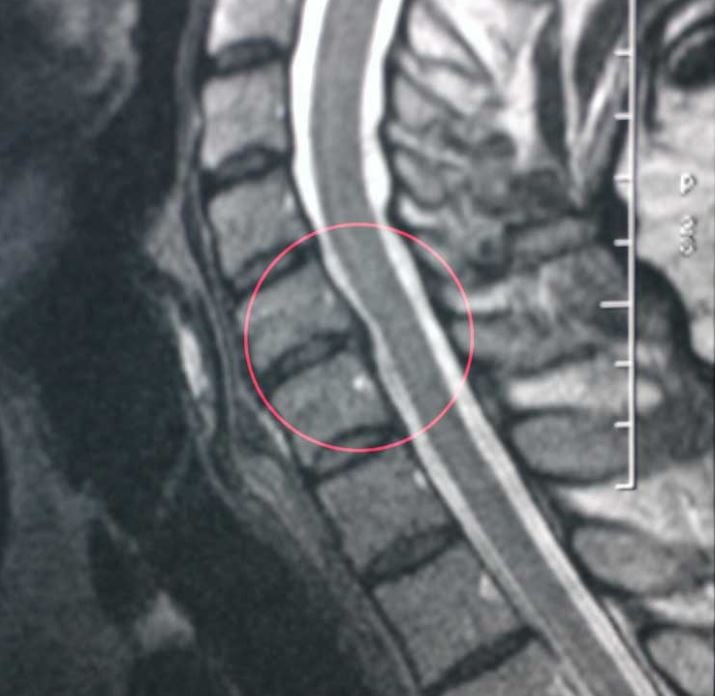

Если шум в ушах вызван остеохондрозом, причина обычно кроется в шейном отделе позвоночника – тиннитус редко возникает при поражении только грудной или поясничной области. Именно через шею проходят артерии и вены, которые питают головной мозг и другие органы головы, забирая из тканей отработанные продукты обмена.

При шейном остеохондрозе эти сосуды часто сдавливаются, возникает нарушение мозгового кровообращения и появляется тиннитус. Вместе с постоянным шумом в ушах отмечаются головные боли головокружения, расстройства зрения, обмороки и другие симптомы.

Если со слухом проблем не выявлено, идите к невропатологу – скорее всего, врач направит вас на УЗИ сосудов головы и шеи, а также на КТ – компьютерную томографию головного мозга и шейного отдела позвоночника.